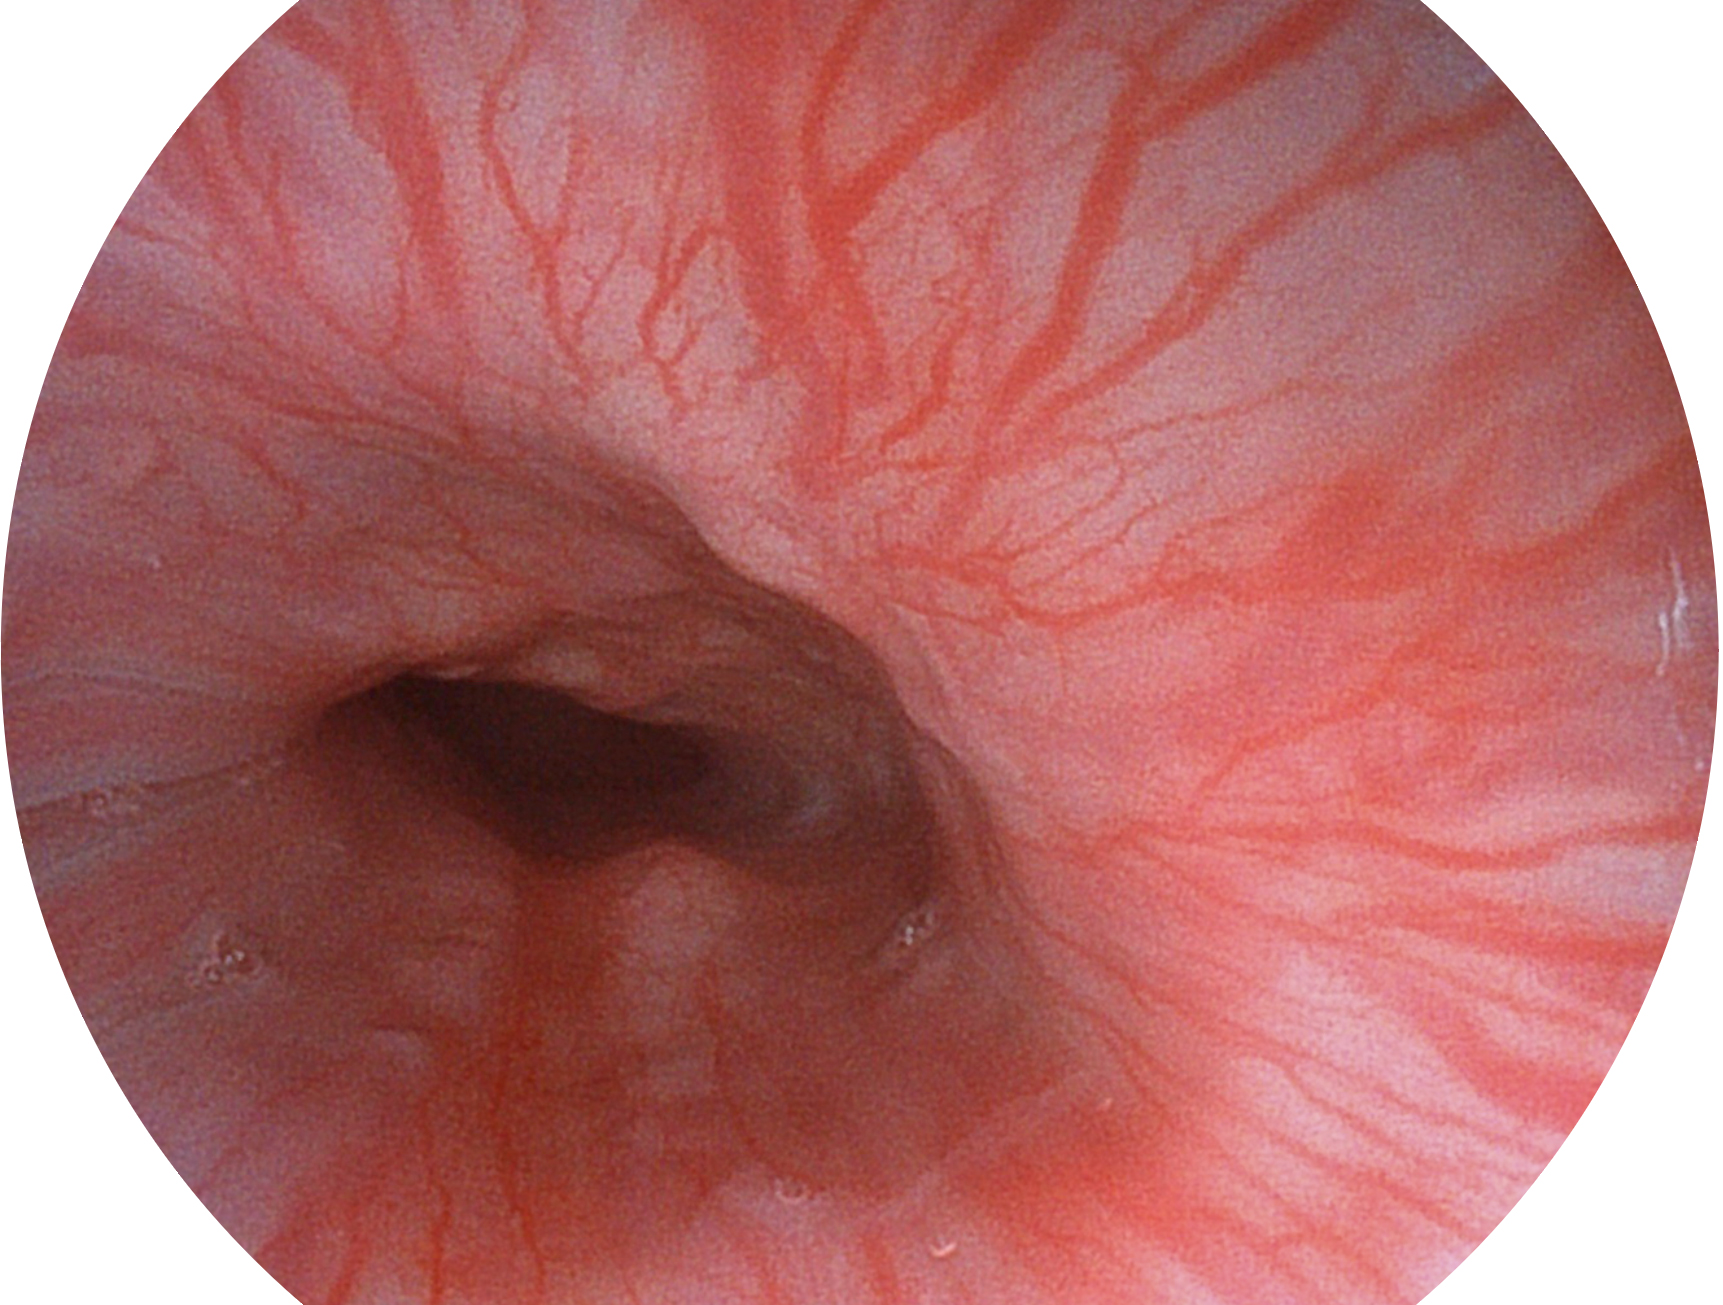

• 白光圖像 VIST圖像